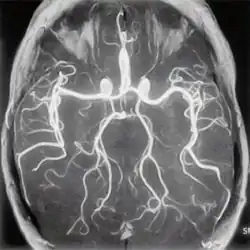

МР-ангиография

Магнитно-резонансная ангиография (МРА) — метод получения изображения просвета сосудов при помощи магнитно-резонансного томографа. Метод позволяет оценивать как анатомические, так и функциональные особенности кровотока. МРА основана на отличии сигнала от перемещающихся протонов (крови) от окружающих неподвижных тканей, что позволяет получать изображения сосудов без использования каких-либо контрастных средств — бесконтрастная ангиография (фазово-контрастная МРА и время-пролётная МРА). Для получения более чёткого изображения применяются особые контрастные вещества на основе парамагнетиков (гадолиний).